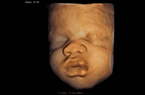

Face foetale en 3D, pivotante Visage lunaire  lunaire pivotante : 37 SA